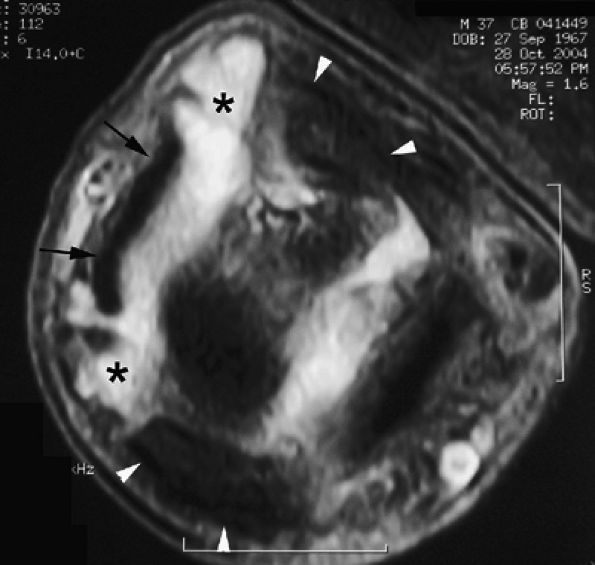

FIGURE 11.47 ● Jersey finger. (A) Sagittal T2-weighted image. (B) Coronal post-contrast T1-weighted images. (C) Axial T1-weighted image. Distal avulsion of the FDP tendon is shown with the proximal end (white arrows) at the metacarpophalangeal joint (type I). The tendon is wavy in the palm (arrowheads). The empty digital canal (in C) may mimic a remnant tendon, but the FDS tendon (asterisk) is alone in the canal.